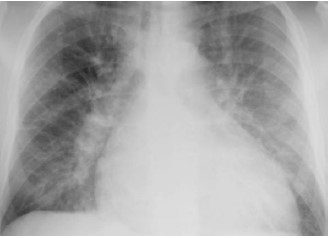

Homem, 71 anos, morador de zona rural no interior do Amazonas, diabético, hipertenso, com diagnóstico de insuficiência cardíaca com fração de ejeção reduzida, todas com bom controle clínico, é encaminhado ao hospital terciário três horas após ter sido vítima de acidente com animal peçonhento.

À chegada, apresenta-se sudoreico, sonolento, com vômitos. Ao exame clínico: PA 76x56, FC 118, FR 26, SatO2 85% a.a., TEC 4s. Propedêutica cardíaca: presença de B3 e de estase jugular a 45º. Propedêutica pulmonar: presença de estertores finos bibasais à ausculta respiratória.

Exames complementares: Glicemia 330 mg/dL, Na 137mEq/L, K 3,5mEq/L, Cl 101 mEq/L, troponina I 2,35mcg/L (VN < 0,014mcg/L), gasometria arterial com pH 7,15, PaO2 57mmHg, PaCO2 28mmHg, bicarbonato 10mEq/L, BE -14.

Segue radiografia de tórax.

Para esse paciente, assinale a opção que apresenta o tipo de acidente e o distúrbio gasométrico.